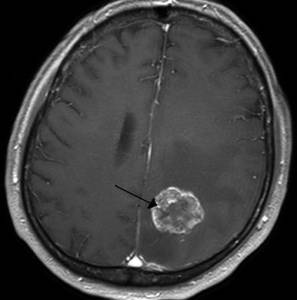

3. Нарастание головной боли может свидетельствовать об опухоли в головном мозге. По мере увеличения опухоли у пациента может возникнуть ощущение движения предметов вокруг себя, нарушается чувство равновесия, бросает в жар, нарушается процесс потоотделения.